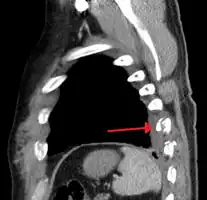

Right sided pneumothorax and rib fractures

Two broken ribs as seen on parasagittal CT